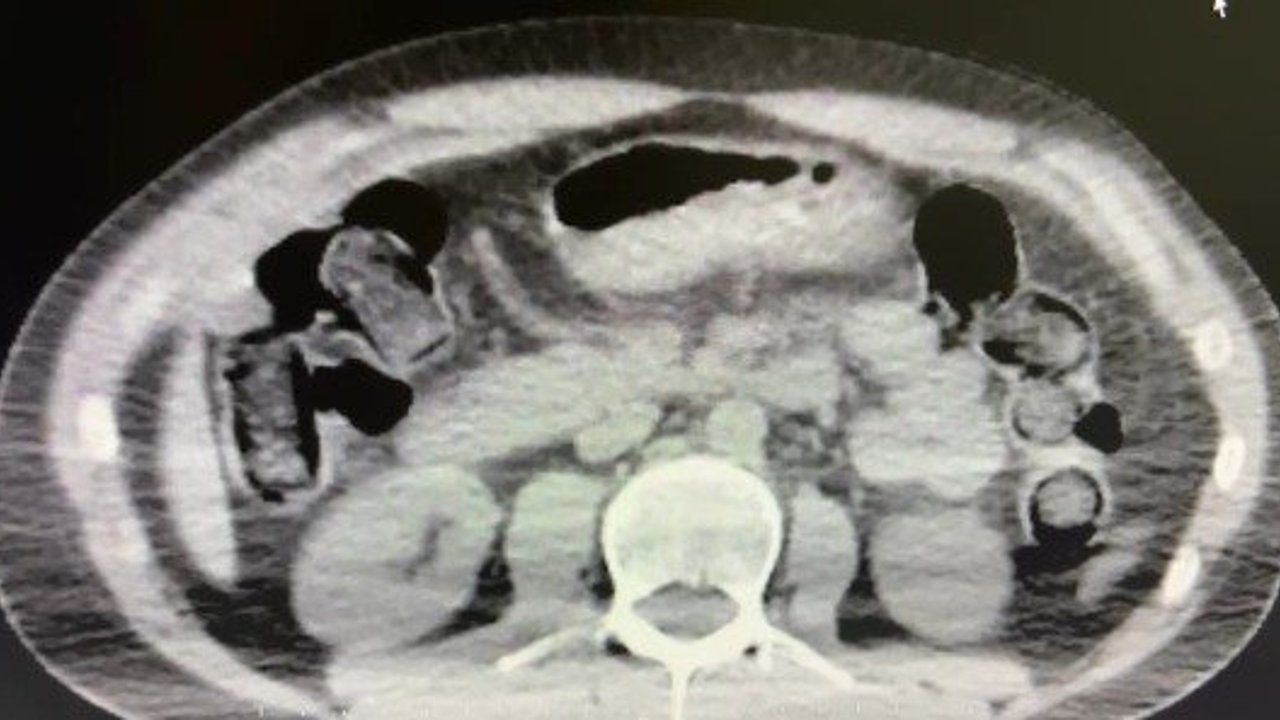

Nevşehir İl Emniyet Müdürlüğü Narkotik Suçlarla Mücadele Şube Müdürlüğü ekipleri, kentte uyuşturucu ve uyarıcı madde ticareti yapmak ve kullanmak suretiyle vatandaşları zehirleyen sokak satıcılarına yönelik çalışma başlattı. Cumhuriyet Başsavcılığı koordinesinde çalışmalarını yoğunlaştıran ekipler, şüpheliler S.B. ve O.R.'nin 'yutma yöntemi' ile kente uyuşturucu madde sevk edeceği bilgisi üzerine operasyon düzenledi. Şüphelilerin ikametlerinde ve araçlarında yapılan aramada 101 kapsül halinde 722 gram uyuşturucu madde, 1 adet hassas terazi, uyuşturucu madde sevkiyatında yutma yönteminde kullanılan muhtelif materyaller, uyuşturucu madde ticaretinden elde edilen 20 bin 210 TL, bin 320 euro ve 10 ABD doları ele geçirildi. Emniyetteki işlemlerinin ardından adliyeye sevk edilen 2 şüpheli, çıkarıldıkları mahkemece tutuklanarak cezaevine gönderildi.